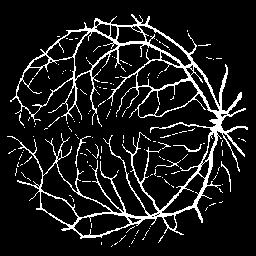

Vessel Extraction

Experiments are implemented on the Digital Retinal Images for Vessel Extraction database (DRIVE) proposed for studies on the extraction of blood vessels (Staal et al. 2004). Models are trained after reshaping all data at 256256 size. Rand score and information theoretic score is also used as evaluation metrics.

The following provides quantitative comparisons of three FCNs respectively. Example results on various image-to-image mapping tasks are shown in Figure 2.

Table 2 lists the best evaluation results. It shows that our model performs on par with U-Net and better than FCN-16s.